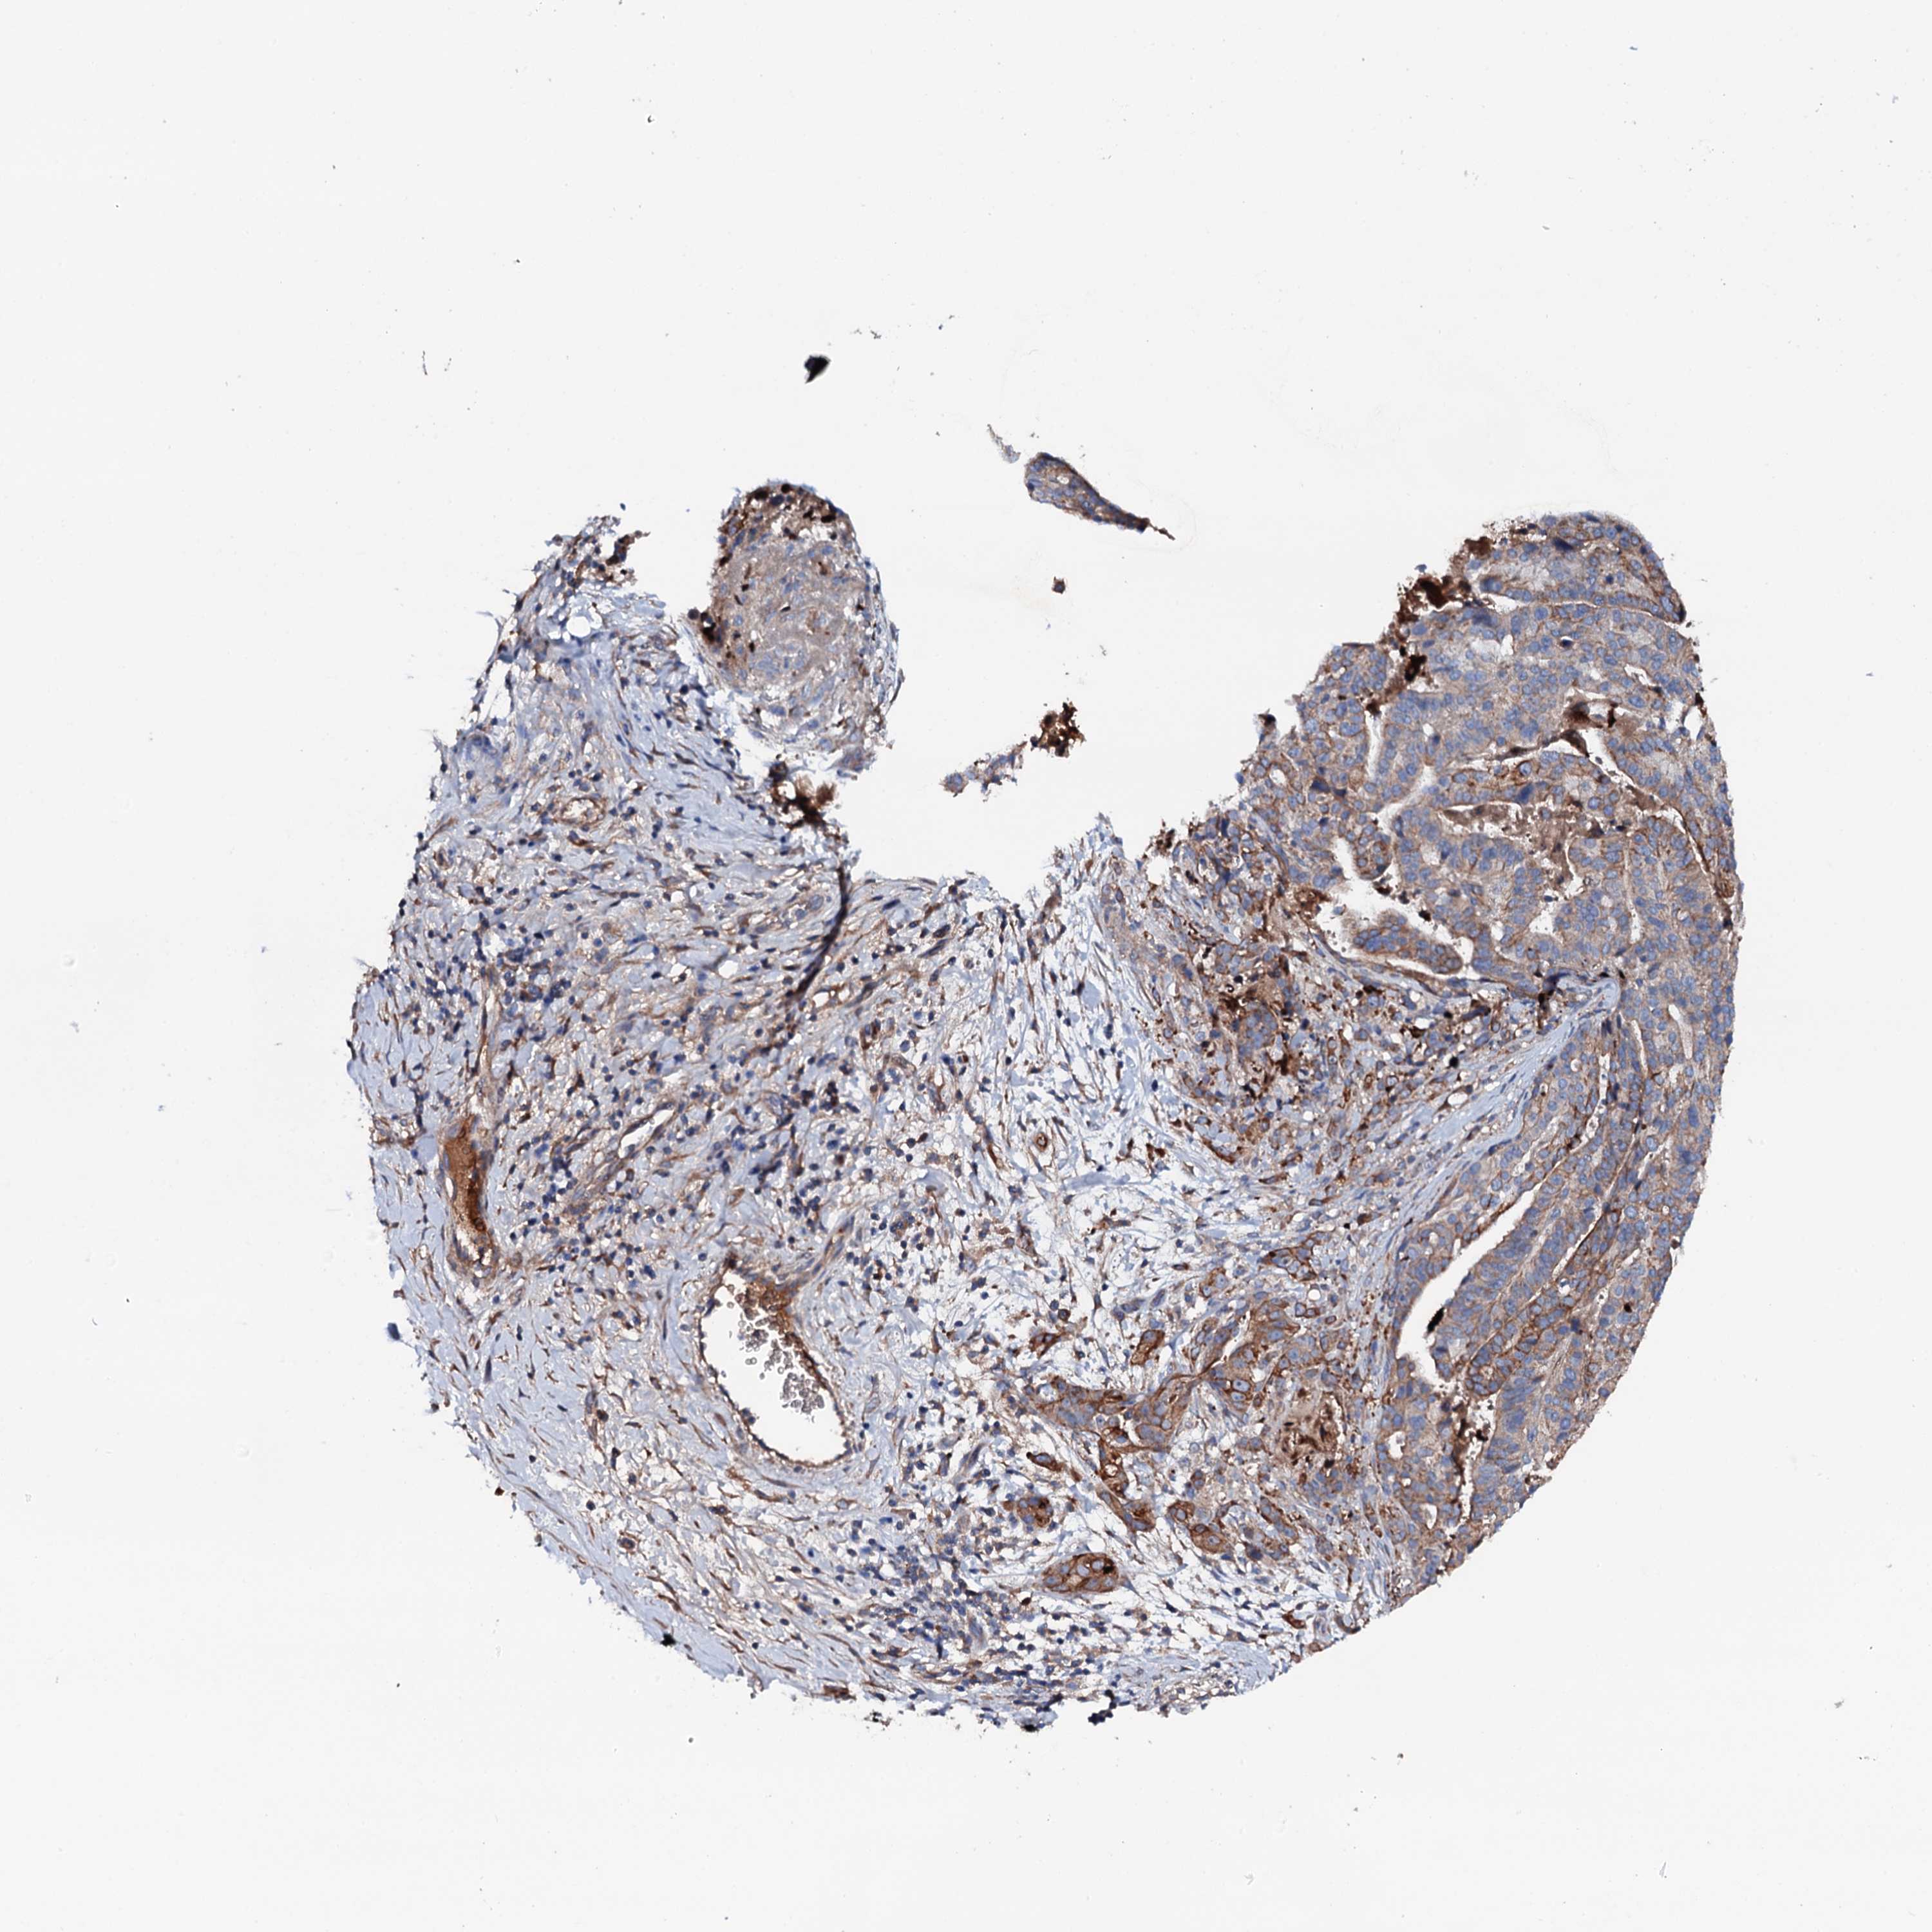

STOMACH CANCER - Protein expressioni

A mouse-over function shows sample information and annotation data. Click on an image to view it in a full screen mode. Samples can be filtered based on level of antibody staining by selecting one or several of the following categories: high, medium, low and not detected. The assay and annotation is described here.

Note that samples used for immunohistochemistry by the Human Protein Atlas do not correspond to samples in the TCGA dataset.

Antibody stainingi

Antibody staining in the annotated cell types in the current human tissue is reported as not detected, low, medium, or high, based on conventional immunohistochemistry profiling in selected tissues. This score is based on the combination of the staining intensity and fraction of stained cells.

Each image is clickable and will lead to virtual microscopy that enables deeper exploration of all samples and also displays staining intensity scores, fraction scores and subcellular localization as well as patient and tissue information for each sample.

Antibody HPA020873

Antibody HPA040413

Staining

High

Medium

Low

Not detected

Intensity

Strong

Moderate

Weak

Negative

Quantity

>75%

75%-25%

<25%

None

Location

Nuclear

Cytoplasmic/membranous

Cytoplasmic/membranous,nuclear

Adenocarcinoma, NOS

Adenocarcinoma, High grade